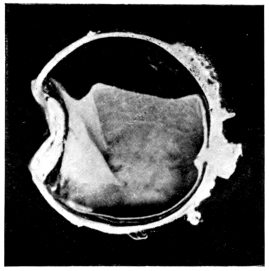

PLATE III.

16.

ABUNDANT EXUDATE INTO VITREOUS CAVITY

curly bracket span

42

17.

LENS FIRMLY FIXED BY ORGANIZED EXUDATE

18.

LENS FIRMLY FIXED BY ORGANIZED EXUDATE, BUT IN UNUSUAL POSITION

19.

TOTAL DETACHMENT OF RETINA, WITH CYST FORMATION

20.

RECLINED LENS LYING IN FRONT OF THE HYALOID BODY

21.

RECLINED LENS LYING IN FRONT OF THE HYALOID BODYxii